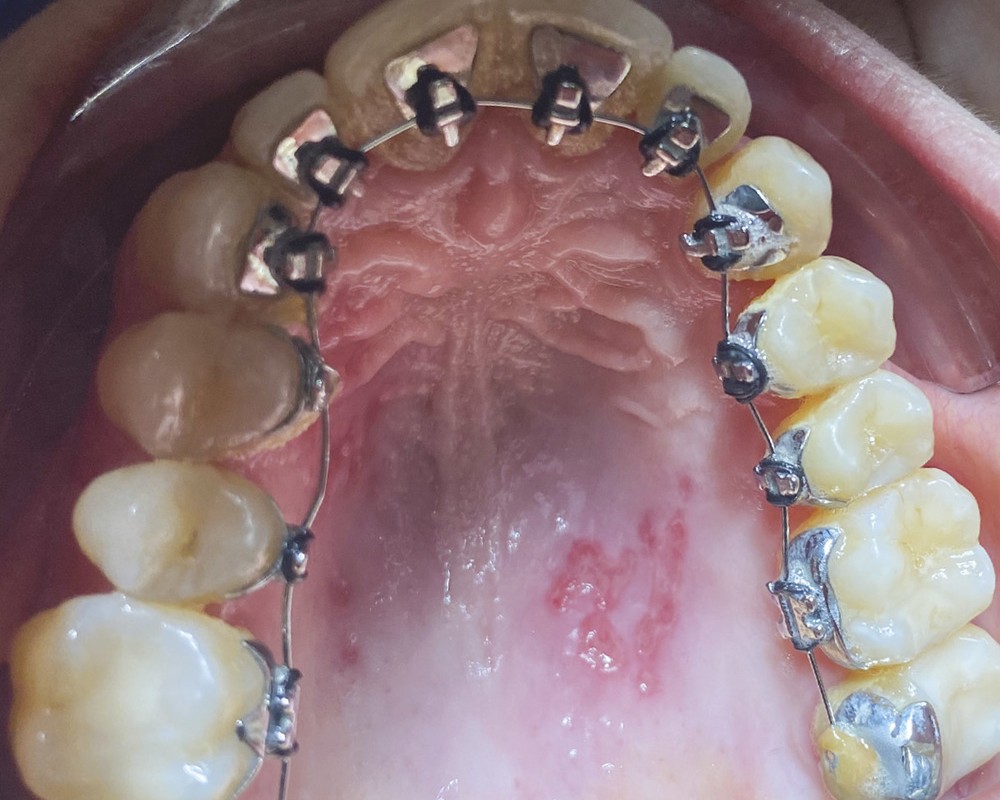

À l’examen clinique, j’observe une lésion rouge et des vésicules sur le palais (fig. 1). L’interrogatoire révèle que Madame L. est en traitement pour une lésion cancéreuse à l’anus depuis huit semaines. Elle a subi vingt-cinq séances de radiothérapie et un traitement de curiethérapie la semaine précédant la crise.

N’ayant jamais observé ce type de lésion, je prends des photos que je transfère à mon correspondant stomatologue, qui diagnostique une lésion herpétique. Cette lésion est favorisée par la dépression immunitaire créée par les traitements des cancers.